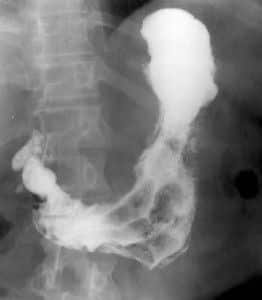

• ULCUS DUODENAL. DOS NICHOS